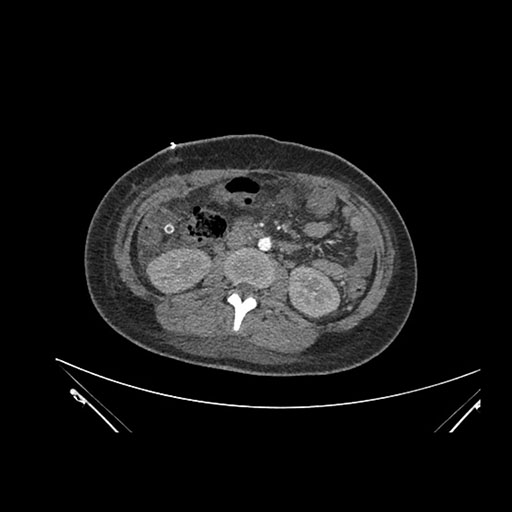

Axial Arterial

Axial Venous